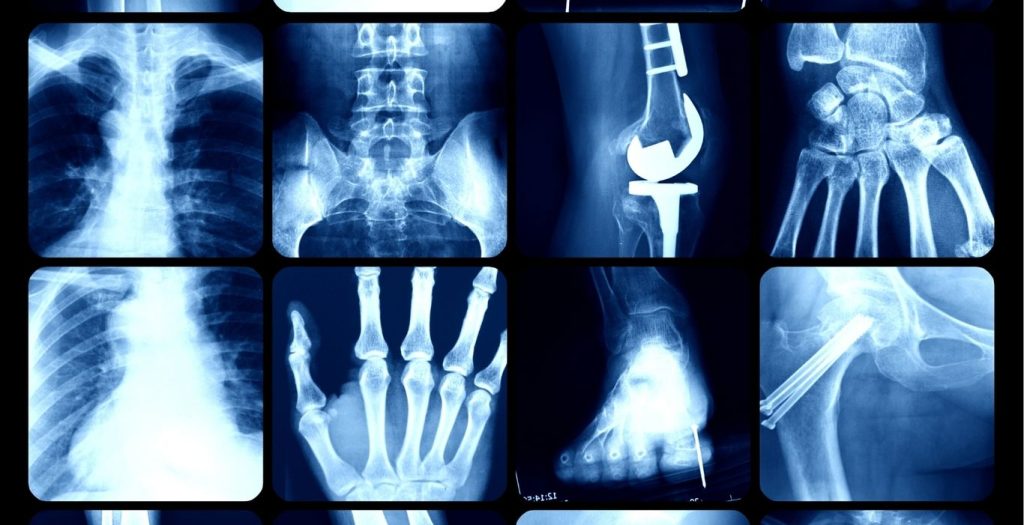

चोट या शारीरिक परेशानी के दौरान डॉक्टर अक्सर X-Ray, CT Scan और MRI जैसे इमेजिंग टेस्ट कराने की सलाह देते हैं। ये तीनों टेस्ट शरीर के आंतरिक अंगों और संरचनाओं का अध्ययन करने के लिए उपयोग किए जाते हैं, लेकिन इनकी तकनीक और उपयोग में महत्वपूर्ण अंतर है। आइए, समझते हैं कि इन परीक्षणों का उपयोग कब किया जाता है और इनमें क्या अंतर होता है।

X-Ray: हड्डियों और फेफड़ों की समस्याओं के लिए

X-Ray एक तेज और सस्ता इमेजिंग विकल्प है, जो मुख्य रूप से हड्डियों और फेफड़ों की समस्याओं की जांच के लिए उपयोग किया जाता है। इसका उपयोग हड्डियों में फ्रैक्चर, दांतों की समस्याओं, और फेफड़ों की बीमारियों (जैसे निमोनिया) का पता लगाने के लिए किया जाता है। हालांकि, यह तकनीक सॉफ्ट टिश्यूज (जैसे मांसपेशियां) की इमेज को स्पष्ट रूप से नहीं दिखा पाती है।

हड्डियों में फ्रैक्चर का पता लगाने के लिए।

फेफड़ों में समस्याओं जैसे टीबी या निमोनिया की जांच।

दांतों की स्थिति का आकलन।

तेज और सस्ता।

हड्डियों की स्पष्ट इमेज प्रदान करता है।

खतरे

सॉफ्ट टिश्यूज की इमेज कम स्पष्ट।

हल्की रेडिएशन का खतरा।